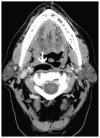

Cross-sectional imaging plays an important role in the evaluation of the retropharyngeal space (RPS) and the prevertebral space (PVS). Because of their deep location within the neck, lesions arising within these spaces are difficult, if not impossible, to evaluate on clinical examination. This article details the cross-sectional anatomy and imaging appearances of primary and secondary diseases involving the RPS and PVS, including metastasis and spread from adjacent spaces. The role of image-guided biopsy is also discussed.